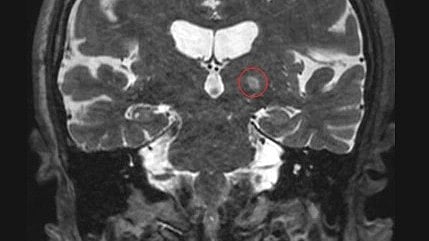

MRI of a patient treated for essential tremor using focused ultrasound, with the targeted part of the brain circled in red. Jmarchn, CC BY-SA 3.0 , via Wikimedia Commons

It is only after scientists made key advances in imaging technology and acoustic physics in recent years that the promise of ultrasound is being realized in the clinic. Hundreds of clinical trials aimed at treating dozens of conditions have been completed or are ongoing. Researchers have found notable success on a condition called essential tremor, which leads to uncontrolled shaking, usually of the hands. Focused ultrasound treatments for essential tremor are now performed routinely at many locations around the world.